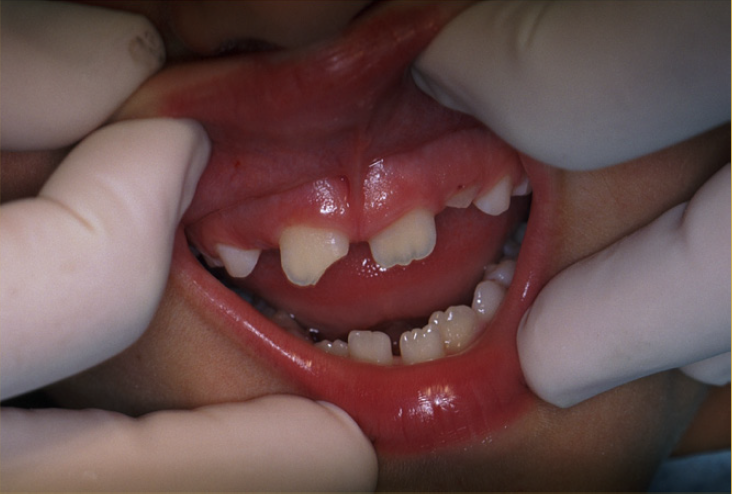

Tooth Intrusion

Tooth intrusion occurs when the tooth has been driven into the alveolar process due to an axially directed impact (Figure 3). This is the most severe form of displacement injury. Athletes with intrusively luxated teeth should be immediately removed from play and transported to a sports emergency dentist.44

Pulpal necrosis occurs in 96% of intrusive displacements and is more likely to occur in teeth with fully formed roots. Immature root development will usually mean spontaneous re-eruption. Mature root development will require repositioning, surgery, and splinting or orthodontic extrusion. Treat relatively quickly since the pulp usually becomes necrotic - this can be treated with temporary filling of calcium hydroxide paste followed by root canal therapy.

Fig 3. Images of Intrusion

Figure 3